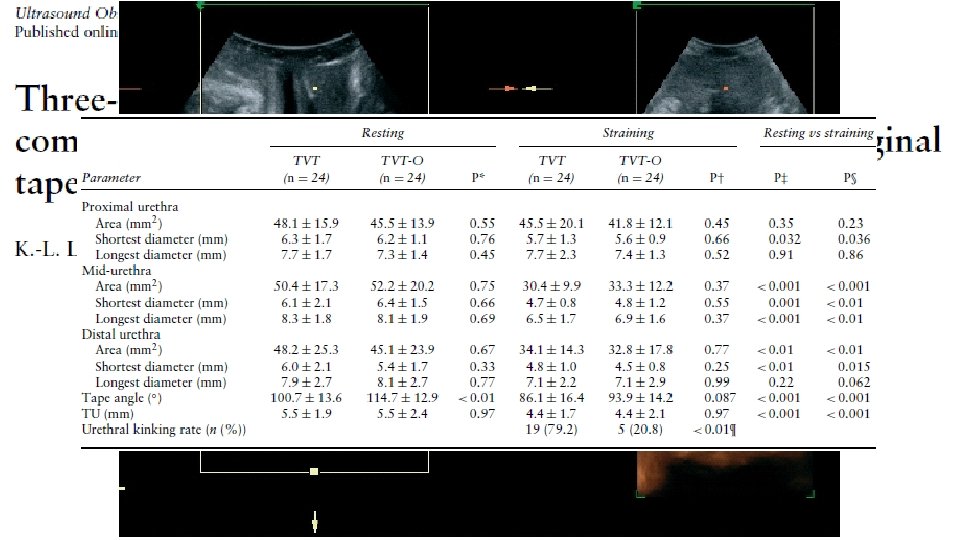

BASİT SÜİ OLGULARINDA İLK SEÇENEK CERRAHİ (KANIT DÜZEYİ 1 ÖNERİ DERECESİ A) TVT MİDÜRETRAL SLİNGLER TOT